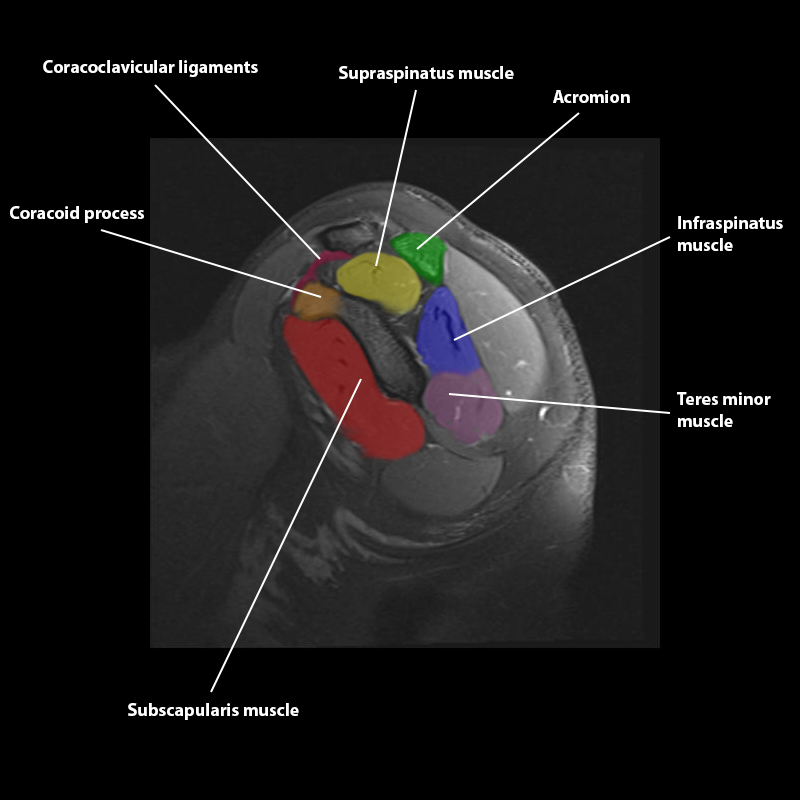

Shoulder MRI Anatomy